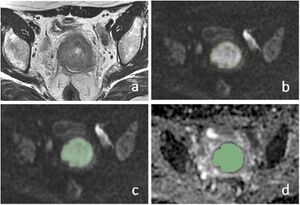

Whole Lesion Histogram Analysis of Apparent Diffusion Coefficients on MRI Predicts Disease-free Survival in Locally Advanced Squamous Cell Cervical Cancer after Radical Chemo-radiotherapy

Publication: BMC Cancer. 2019 Nov 15;19(1):1115. PMID: 31729974 | PDF Authors: Zhao B, Cao K, Li XT, Zhu HT, Sun YS. Institution: Department of Radiology, Key Laboratory of Carcinogenesis and Translational Research, Ministry of Education, Peking University Cancer Hospital and Institute, Beijing, China. Abstract: BACKGROUND: The aim was to investigate the prognostic value of MR apparent diffusion coefficients (ADC) using histogram analysis (HA) in predicting disease-free survival (DFS) of cervical cancer after chemo-radiation therapy. METHODS: We retrospectively analyzed 103 women with pathologically proven squamous cell uterine cancer who received chemo-radiation therapy between 2009 and 2013. All patients were followed up for more than 2 years. Pre-treatment MR images were retrieved and imported for HA using an in-house developed software program based on 3D Slicer. Regions of interest of whole tumors were drawn manually on DWI with reference to T2WI. HA features (mean, max, min, 50, 10, 90%, kurtosis, and skewness) were extracted from apparent diffusion coefficient (ADC) maps and compared between the recurrence and non-recurrence groups after the 2-year follow-up. Univariate and multivariate Cox regression analysis was used to correlate ADC HA features and relevant clinical variables (age, grade, maximal diameter of tumor, FIGO stage, SCC-Ag) with DFS. RESULTS: One hundred three patients with stage IB-IV cervical cancers were followed up for 2.0-94.6 months (median 48.9 months). Twenty patients developed recurrence within 2 years. In the recurrence group, the min (P = 0.001) and 10% (P = 0.048) ADC values were significantly lower than those of the non-recurrence group. Univariate and multivariate Cox regression analysis revealed that ADCmin (P = 0.006, HR = 0.110) was significantly correlated with DFS. CONCLUSION: Pre-treatment volumetric ADCmin in histogram analysis is an independent factor that is correlated with DFS in cervical cancer patients treated with chemo-radiation therapy. |

Manual segmentation of ROIs in cervical lesion and schematic diagram of parameters. a–c Referring to T2WI and DWI, ROIs were drawn manually slice by slice on DWI images along the edge of the lesions in order to cover as much tumor area as possible without excluding cystic or necrotic areas. d The same ROIs were registered to ADC maps. |